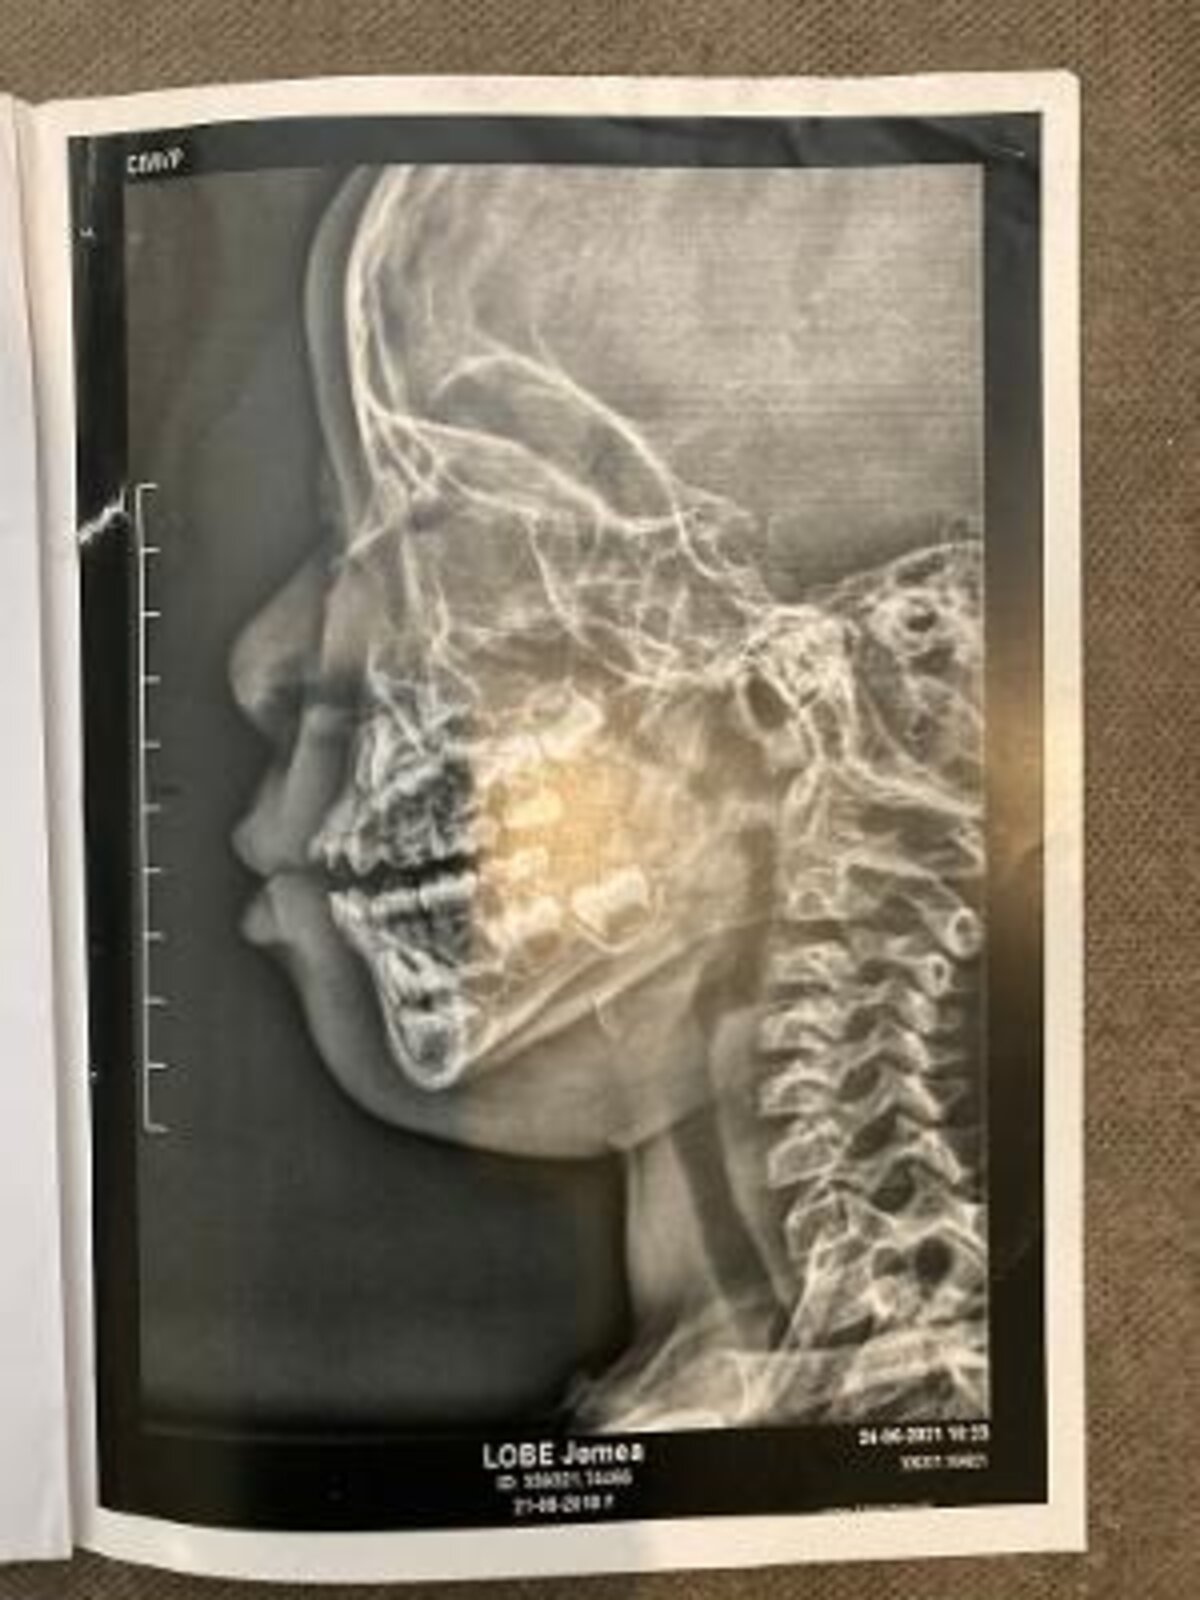

Nous subissons des radiations électromagnétiques toutes les nuits, qui ont eu de graves conséquences sur son système respiratoire comme le prouve la radio ci-jointe.

Illustration 1